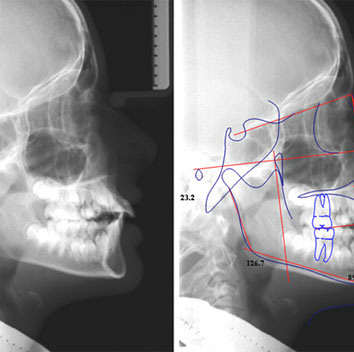

una teleradiografia laterale (che serve per eseguire le misurazioni cefalometriche utili alla formulazione di un piano di trattamento ortodontico)

Con questi esami lo specialista esegue un tracciato cefalometrico, e se necessario inizia un trattamento ortopedico funzionalizzante che utilizza un apparecchio mobile (i bambini lo possono mettere e togliere da soli) con il quale si può guidare la crescita dei denti in posizione corretta, guidare la crescita delle basi ossee e correggere abitudini viziate come succhiare il dito e respirare con la bocca aperta.